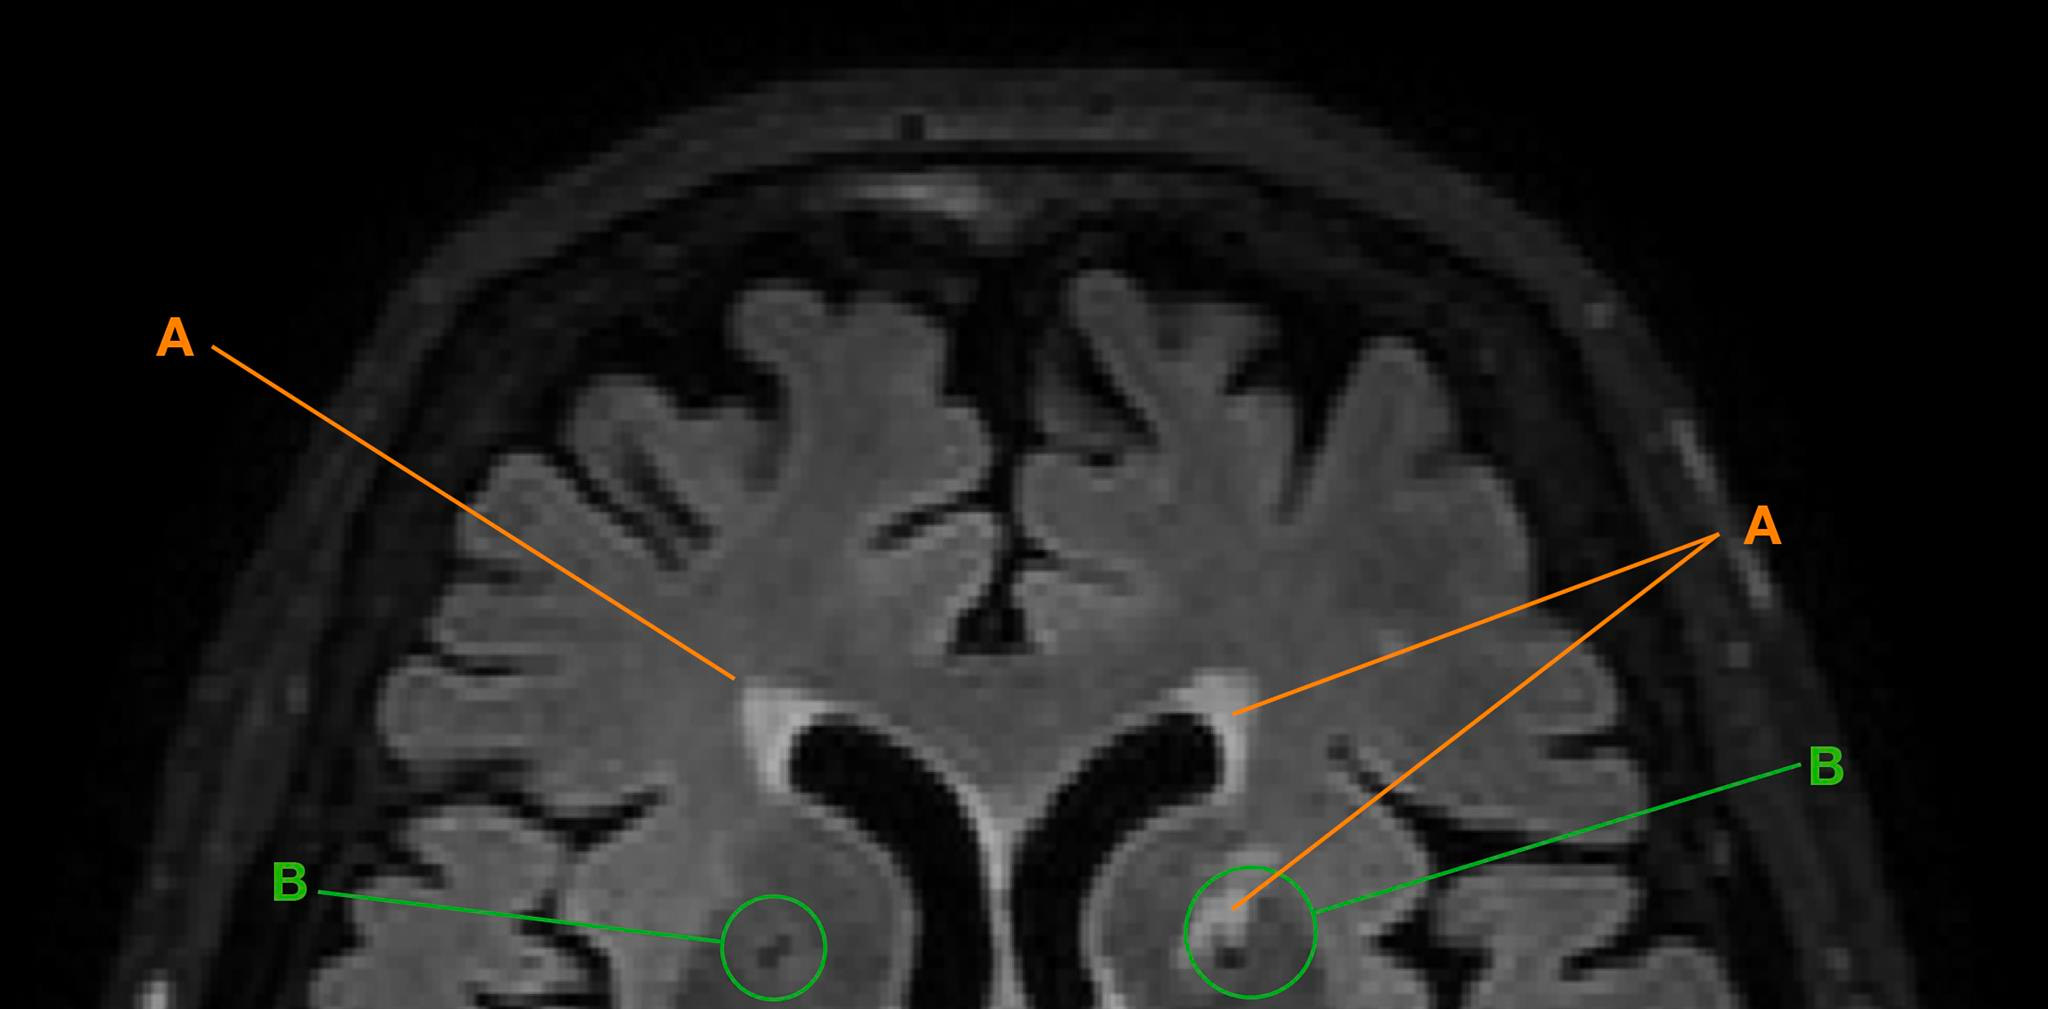

In her PhD thesis, first author Isabel Hotz used novel automatic methods among others to study so-called lacunes and white matter hyperintensities. These degenerative processes showed up as “black holes” and “white spots” on the digital images. The reasons for this are not yet known and may have to do with small, unnoticed cerebral infarcts, reduced blood flow or loss of nerve pathways or neurons. This can limit a person’s cognitive performance, in particular when degeneration affects key regions of the brain.

The findings revealed that over the course of seven years, senior citizens with an academic background showed a significantly lower increase in these typical signs of brain degeneration. “In addition, academics also processed information faster and more accurately – for example, when matching letters, numbers of patterns. The decline in their mental processing performance was lower overall,” summarizes Hotz.